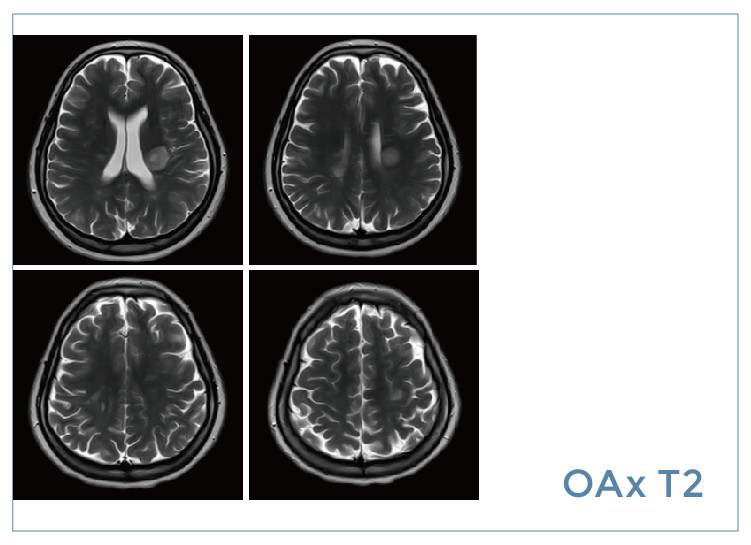

【朗润影像档案】20190823磁共振影像病例结果讨论